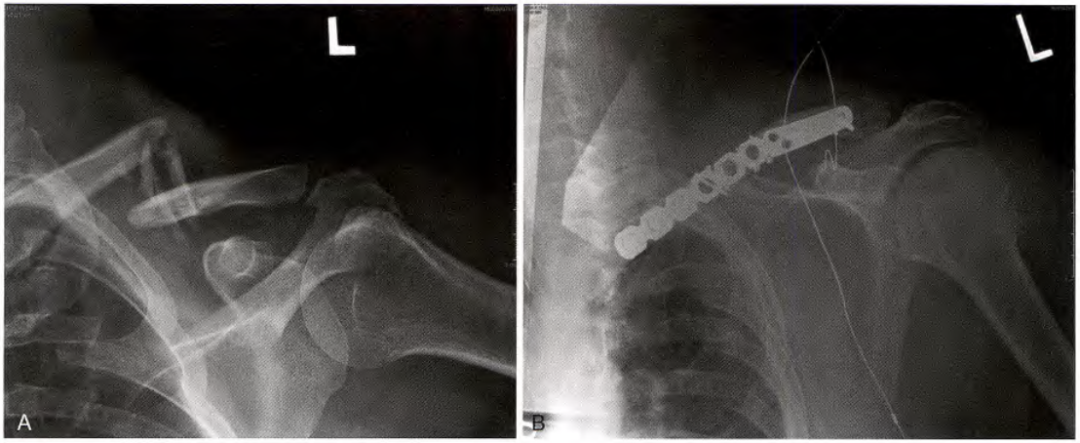

钢板和螺钉固定

A.锁骨骨折, B.前方钢板固定